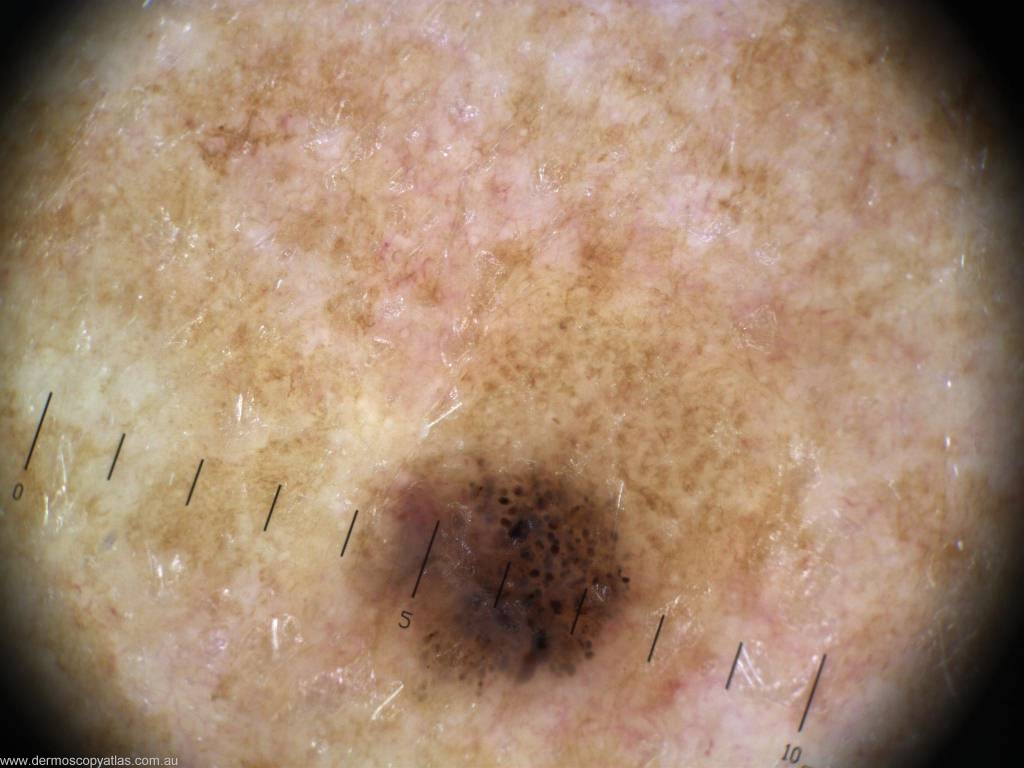

Case 11 Female aged 53. Routine check. No patient history. L arm.

Question: What is your diagnosis? Consider Melanoma in situ, Seborrhoeic keratosis, Invasive melanoma,Benign compound nevus, Dysplastic nevus, Pigmented BCC and Spitz nevus.

Answer: Histology: L2 0.5mm thick, Superficial spreading melanoma arising within a dysplastic compound naevus